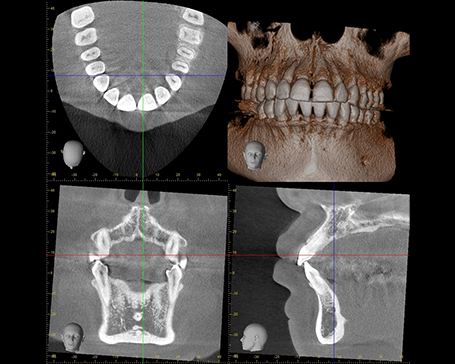

医療設備と技術

私たちの歯科医院では、精度と快適性を重視した医療機器を導入し、質の高い治療に力を入れています。